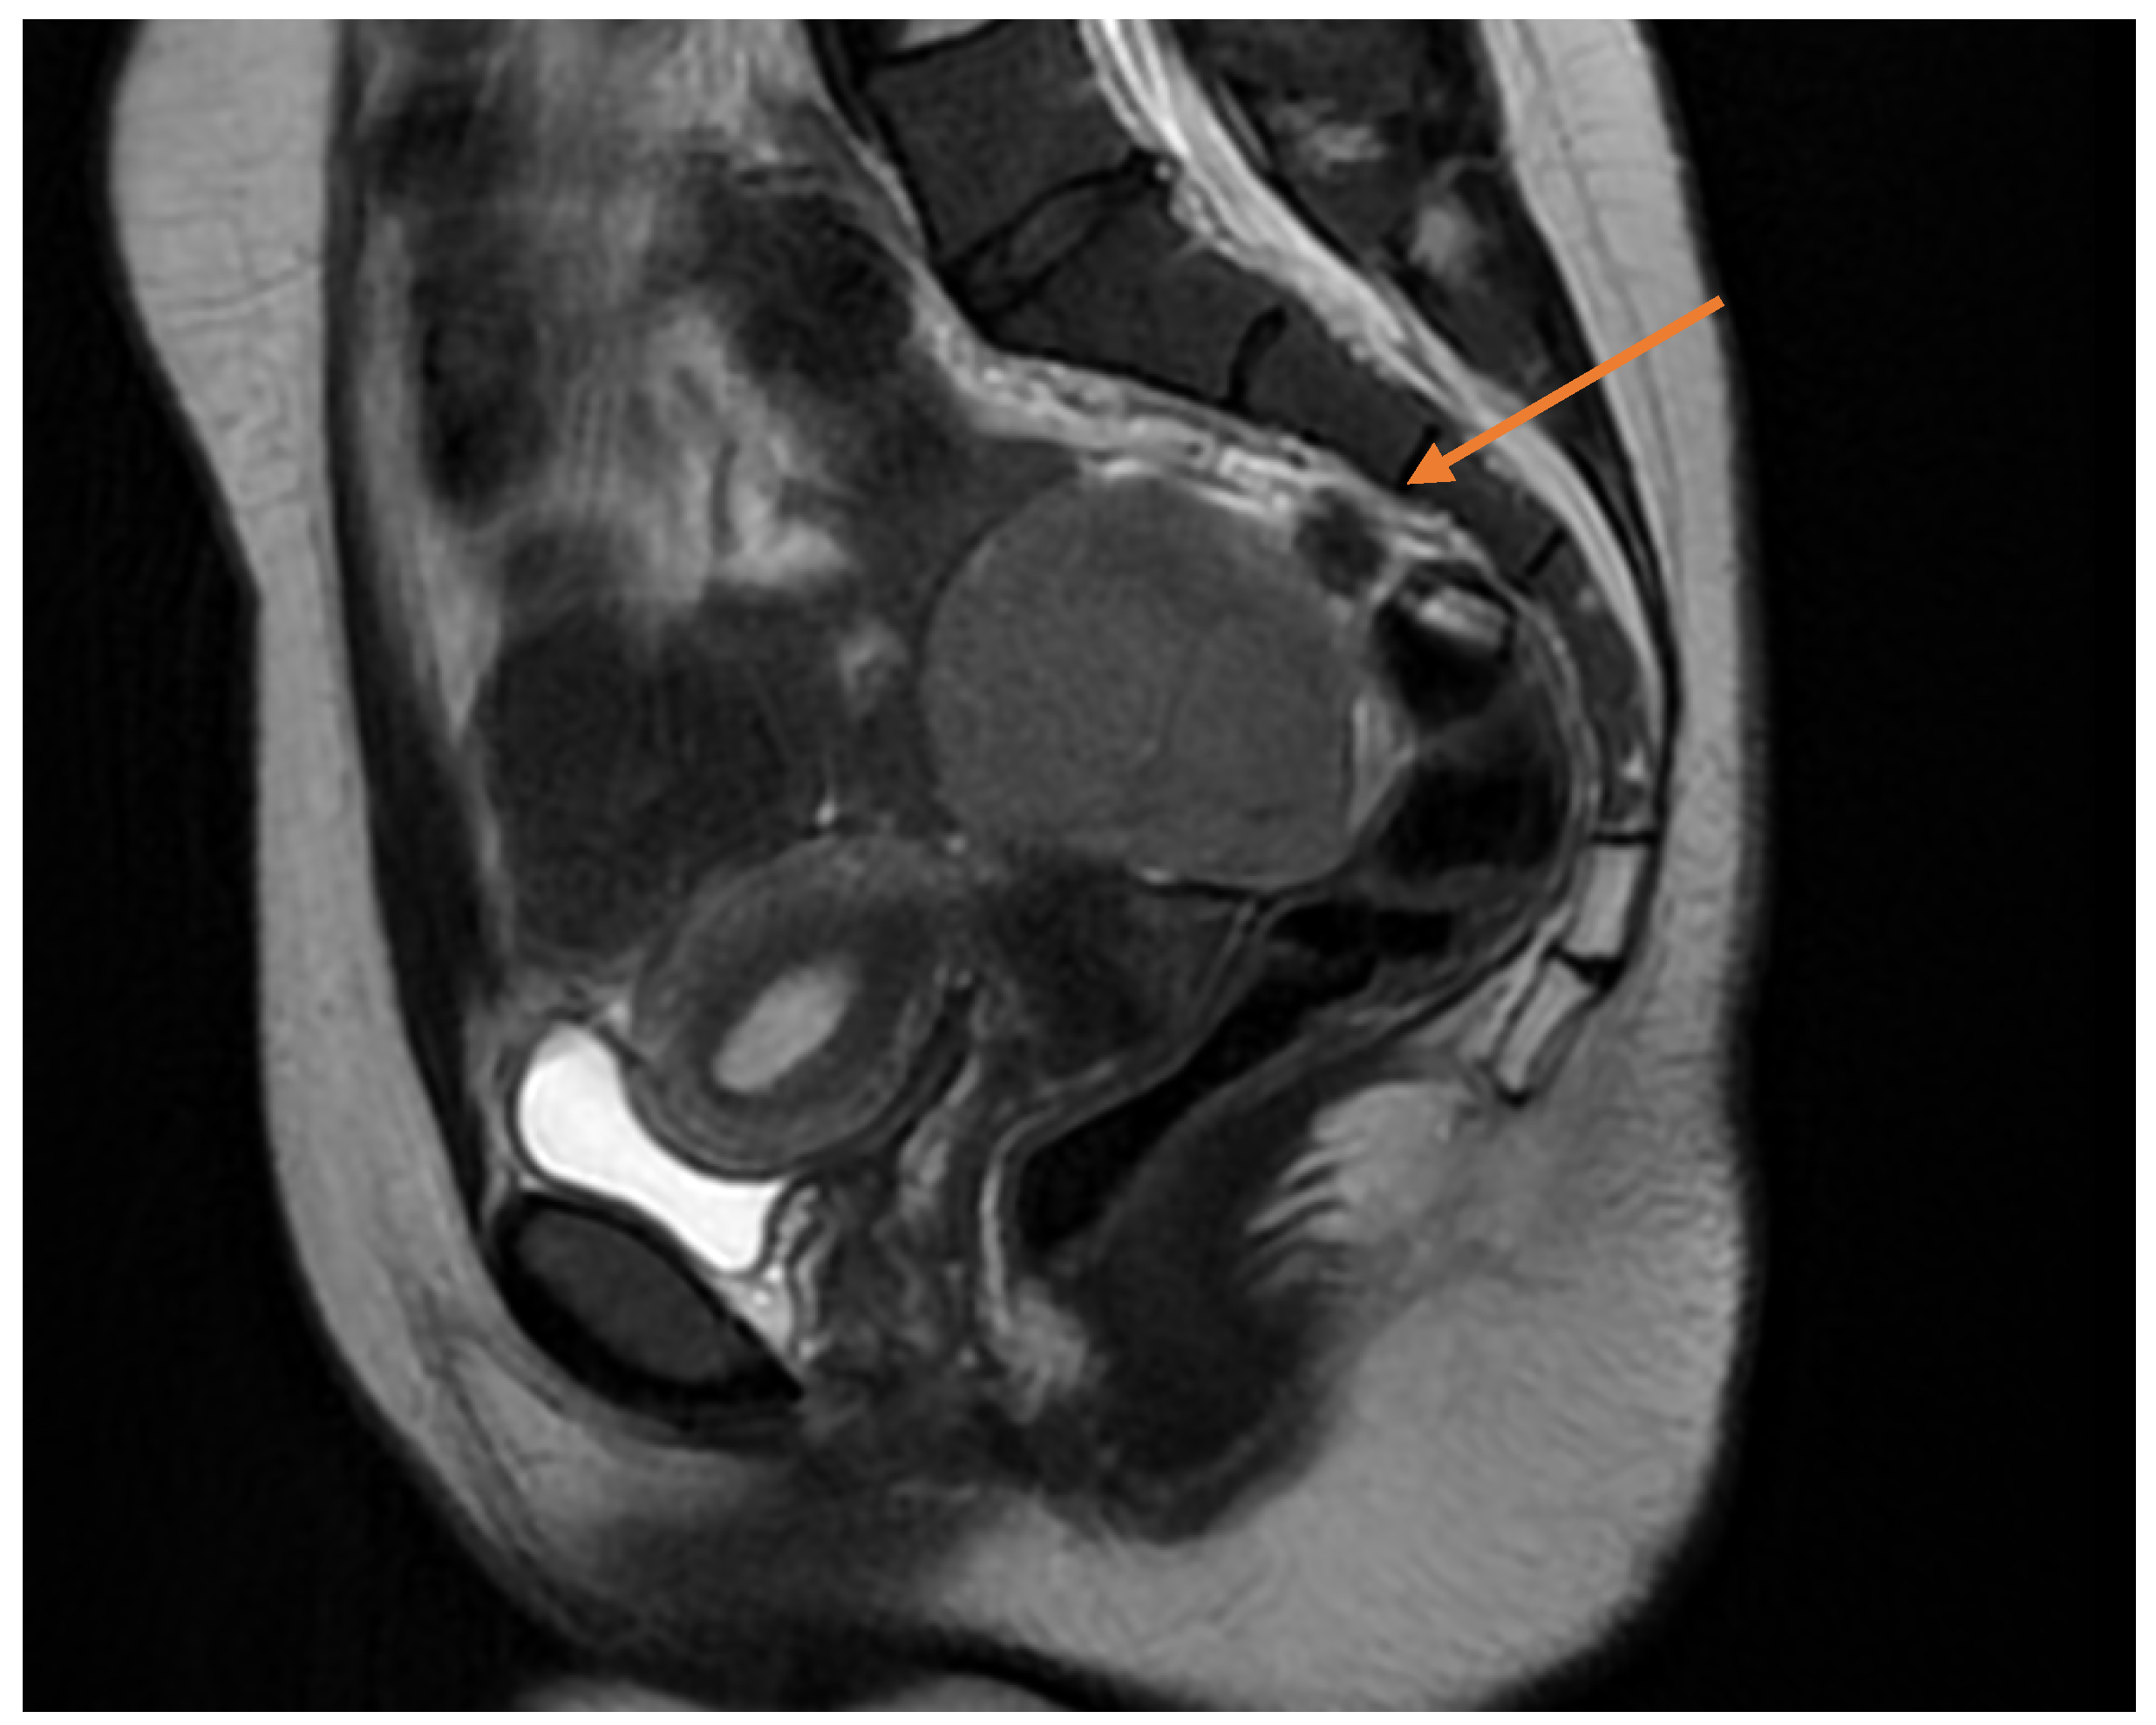

Pelvic MRI demonstrated a well-circumscribed, encapsulated, septated round-oval mass (62 × 74 mm) situated in the pouch of Douglas, adjacent to the left adnexa. The lesion contained multiple small cystic areas and a nodular component with low signal intensity on T2- and T2FS-weighted sequences and high signal intensity on T1, findings consistent with intratumoral hemorrhage (Figure 2 and Figure 3). After contrast administration, the solid component of the mass showed vascular enhancement.

Figure 2. Sagittal pelvic MRI (T2-weighted) demonstrating a septated adnexal mass in the pouch of Douglas, with cystic and nodular components suggestive of intratumoral hemorrhage (yellow arrow).